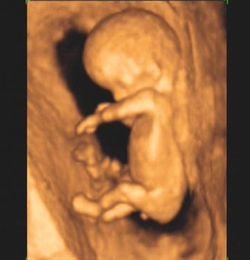

- Pregled u desetoj nedelji zadovoljava dva kriterijuma našeg projekta Daj šansu životu.Onse, pre svega, odnosi na žene koje su u dilemi da li da zadrže ili prekinu trudnoću. Inače, trudnoća od dva i po meseca (10. nedelja) - po zakonu još uvek može da se prekine, ukoliko žena to želi da uradi. Drugi razlog (kriterijum) je što se u osmoj ili, na primer, u devetoj nedelji trudnoće ne vidi tako dobro kao u desetoj - da taj novi život izgleda kao mali čovek. Iako je tada plod dug svega tri centimetra, već u desetoj nedelji ima sve: oči, uši, ruke, noge (što pokazuje 3D ultrazvuk, dok u 4D dimenziji mama i tata vide i prvi „ples“ svoje bebe). Napominjem da besplatan pregled u 10. nedelji mogu da zakažu i obave sve trudnice, bez obzira da li je trudnoća planirana i željena ili se, jednostavno, dogodila.

Nakon što se uverimo da srce ploda kuca i da je sa trudnoćom za taj period sve u redu, zakazujemo pregled u desetoj nedelji, koji je besplatan. Dirljivo je ogromno iznenađenje buduće mame koja tada (u 10. nedelji) vidi koliko je beba porasla za samo dve do tri nedelje, kada je izgledala kao zrno pasulja, a u desetoj je pravi mali čovek!

- Prvo se izmeri bebica, utvrdi se starost trudnoće. Roditelji na ekranu vide da beba ima obe ručice, nožice... I dok roditelji uživaju gledajući svoju bebu na ekranu, doktor želi da se uveri da plod nema nikakvu vidljivu anomaliju. Čak i kada bi trudnica insistirala da plati pregled, misleći da bi tako dobila više informacija, pravo vreme da se gledaju ultrazvučni znaci za Daunov sindrom i sve druge anomalije, kao i za detaljnu anatomiju svih organa (kako spoljašnjih, tako i unutrašnjih) je tek 12. nedelja trudnoće. Napominjem da u 12. nedelji žena po zakonu nema pravo da samoinicijativno odluči da prekine trudnoću. U tom periodu, trudnoća može da se prekine samo ako za to postoji neki medicinski razlog, koji utvrđuje konzilijum lekara.